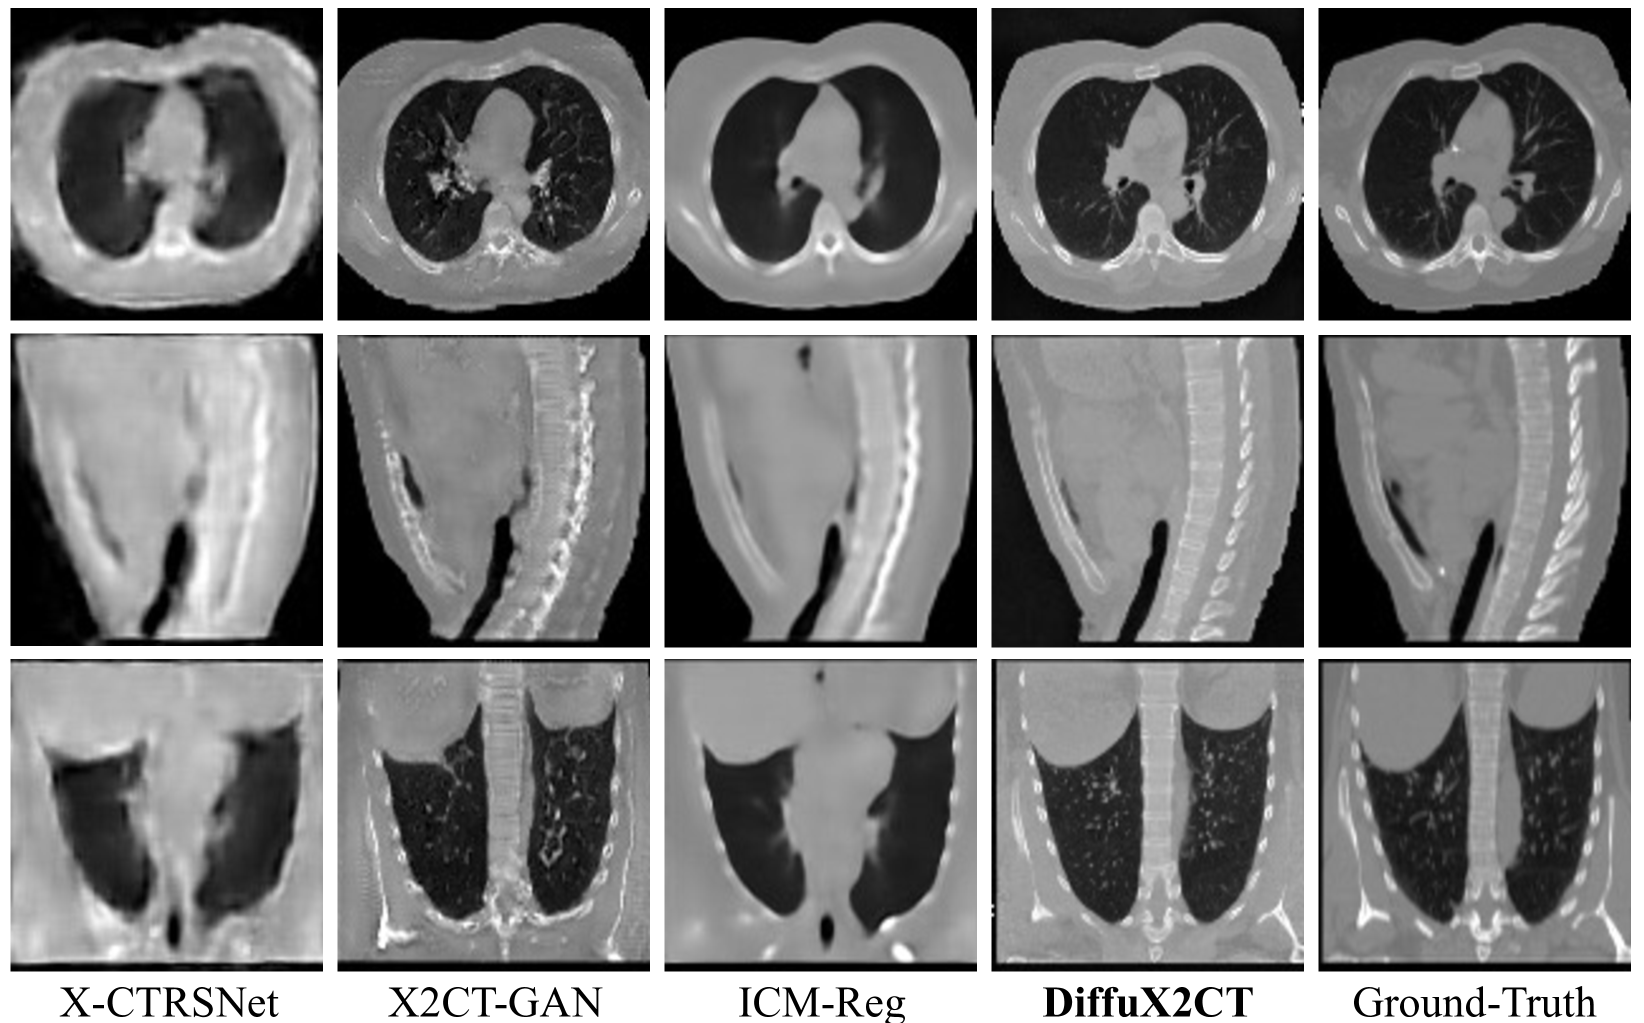

Refer to caption

Figure 3: Qulitative comparisons on the CTSpine1K dataset. From top to bottom, we show the axial, sagittal, and coronal views. Best viewed by zoom in.

Qualitative Results. Fig. 3, Fig. 4, and Fig. 5 show the qualitative comparisons with prior arts on the LIDC-IDRI and CTSpine1K datasets. The results of the regression model X-CTRSNet exhibit inferior sample quality. Although the generative model, X2CT-GAN, can generate sharp textures, it often creates severe artifacts (e.g., incorrect heart shape and lack of aorta and pulmonary artery in Fig. 4) and distortions (i.e. unnatural bone structures in Fig. 5). Our regression version, ICM-Reg, is effective in recovering accurate structures but suffers from over-smoothing textures and lacks high-frequency details. In comparison, our DiffuX2CT is capable of reconstructing clear CT textures and consistent structure with the ground-truth, far superior to the counterpart methods.